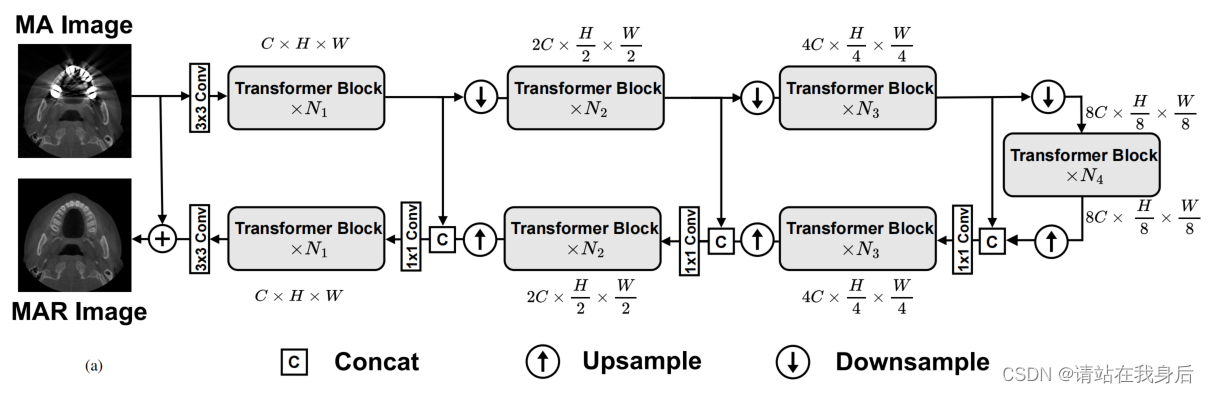

可以看到框架采用Unet,三层编码解码,每层N个变压器块,熟悉的童鞋可以只看维度就可以了

作为有监督网络,训练肯定是采用的退化方法,将添加了金属伪影的输入X 金国3*3卷积提取特征,然后输入第一层编码器输出特征是空间方向的下采样和通道方向的扩展到2C × h/2 × w/2的大小。然后再第二层同样,经过三层分层编码器后,将大小为8C × h8 × w8的输出特征图输入到bottleneck。

在解码器阶段,特征映射在解码器的每个级别上向上采样,并在信道上缩小一半,并与相应级别编码器的特征输出相连接。为了保持不同级别之间的通道维度一致,使用1×1卷积将连接特征的维度从2C降至C,然后再将其馈送到下一级解码器。

不同级别编码器或解码器之间的下采样和上采样操作是通过像素unshuffle/shuffle操作来实现的。将最后一个解码器后的feature map进行3×3卷积融合得到图像残差,将残差R加入到输入图像I中,得到最终的MAR图像I‘ = I + R。